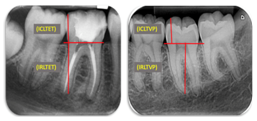

Periapical radiographs were taken for each patient before and after the orthodontic treatment with the use of XCP Dentsply collimators, in order to obtain the most faithful images possible of the dental structures, to avoid the distortion and obtain the best parallelism between the plate and the teeth. The X-ray apparatus of the brand Corix model 70 plus USV-WM was used with an exposure of 0.26 thousandths of a second of the X-rays to the plate. The same radiology assistant and the x-ray machine were used for the two radiographs of each patient. The measurements were taken before and after the orthodontic treatment using Adobe Photoshop CS software. Points and reference lines were placed to perform the measurements (Figure 2). The examination and evaluation of the periapical radiographs was carried out in which the following reference points were used (Figure 3):

Figure 3 Reference points to evaluate external root resorption (modified Llamas et al., 2010).

(ICLTET) initial coronal length in tooth with endodontic treatment

(FCLTET) final coronal length in tooth with endodontic treatment

(ICLTVP) initial coronal length in tooth with vital pulp

(FCLTVP) final coronal length in tooth with vital pulp

(IRLTET) initial root length in tooth with endodontic treatment

(FRLTET) final root length in tooth with endodontic treatment

(IRLTVP) initial root length in tooth with vital pulp

(FRLTVP) final root length in tooth with vital pulp